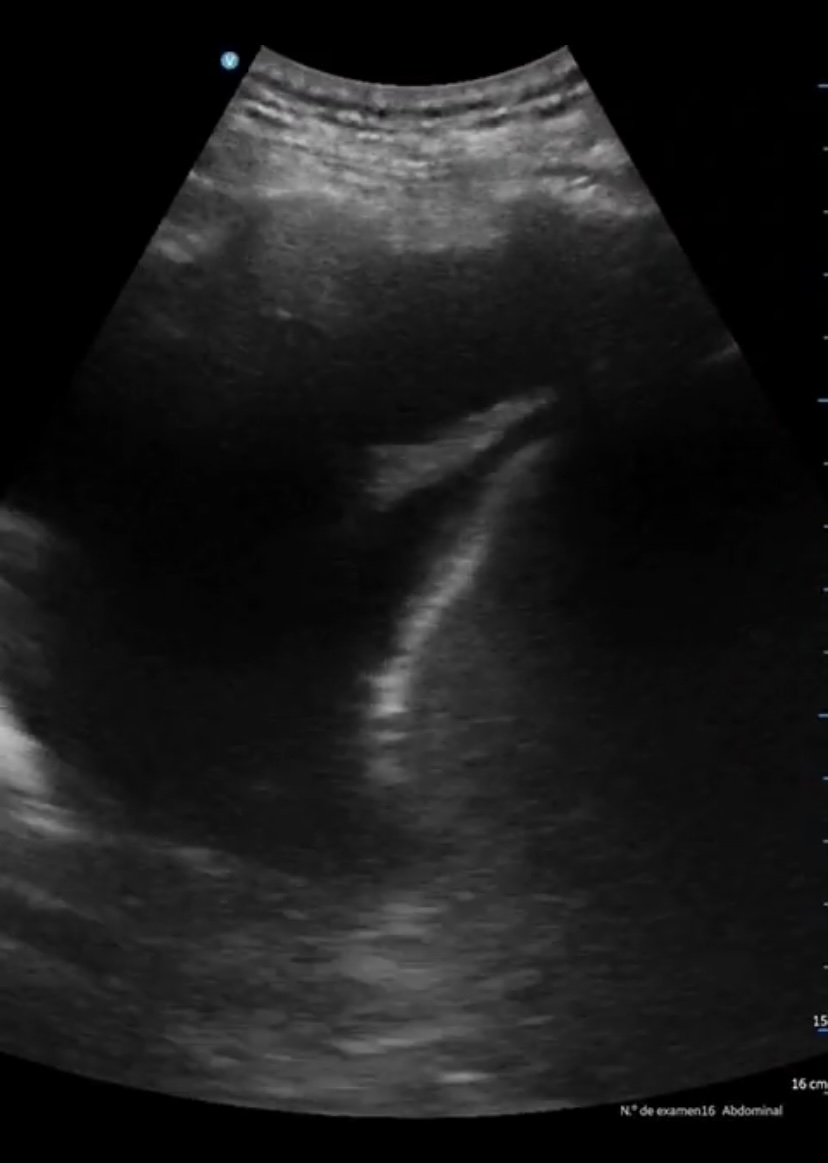

Se aprecia atelectasia lobar media con derrame pleural derecho de unos 150 cc, signo de la medusa. Líneas B en patrón B3 en ambas bases. Cavidades cardiacas normales con correcto funcionamiento valvular, adecuada contractilidad sin indicios de derrame pericárdico. Aumento de vena cava de 2,57 cm no colapsable.

A los 2 días, el paciente presenta empeoramiento de clínica, con disminución SpO2 a 90%, persistencia de fóvea intensa y disnea de reposo. Se revalora ecográficamente encontrando aumento de derrame pleural, ahora 500 cc, una vena cava de 3,27 cm no colapsable y derrame pericárdico. Finalmente se decide derivación hospitalaria.